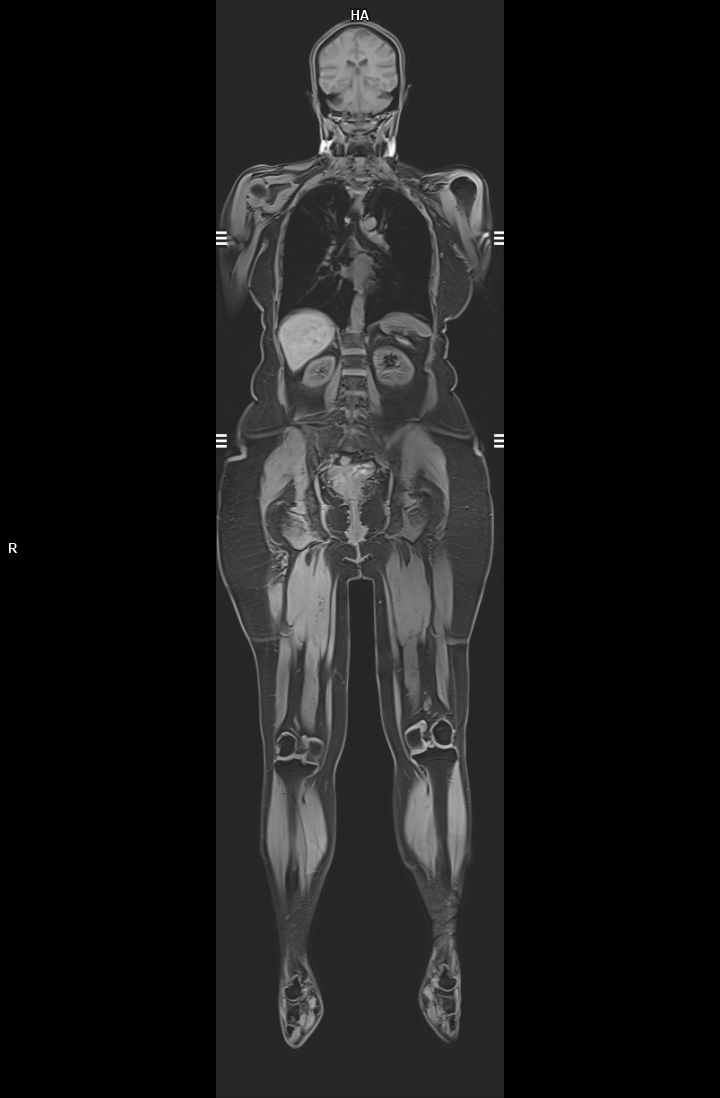

3 Tesla MR Çekim Görüntüleri

• 3 Tesla MR Çekim Görüntüleri